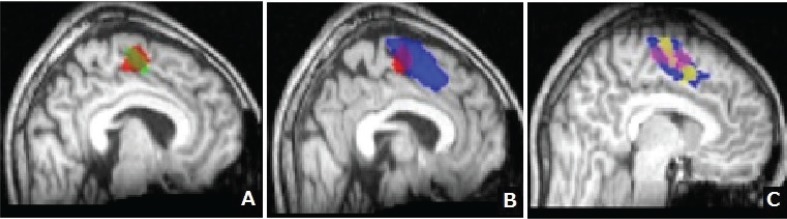

Figure 4 displays the SMA distribution for each task on the basis of group analysis. Most areas of rFT-SMA and lFT-SMA were overlapped (82.3%; Fig. 4A). LDT-SMA shared 54.0% of rFT-SMA and also extended anterior to rFT-SMA (Fig. 4B). Figure 4C shows that LDT-SMA is widest compared to the area of activation induced by other language tasks. Figure 4 summarizes SMA activations in response to all language tasks (language-SMA) were anterior to those to motor tasks (motor-SMA).

Fig. 4.

Supplementary motor area (SMA) distribution for each task based on group analysis. A: Areas shaded in red and green represent the region of SMA activated during right finger tapping (rFT-SMA) and left finger tapping (lFT)-SMA, respectively. The areas activated by these tasks mostly overlapped (approximately 80%). B: Areas shaded red and blue represent rFT-SMA and a region of SMA activated during the lexical decision task (LDT-SMA), respectively. LDT appears to activate a region of the SMA that is wider and more anterior than that activated by rFT. C: Areas shaded in pink and yellow represent a region of SMA activated during reading task (RT-SMA) and verb generation (VG-SMA), respectively. And areas shaded in blue represent LDT-SMA which was overlapped RT-SMA and VG-SMA.